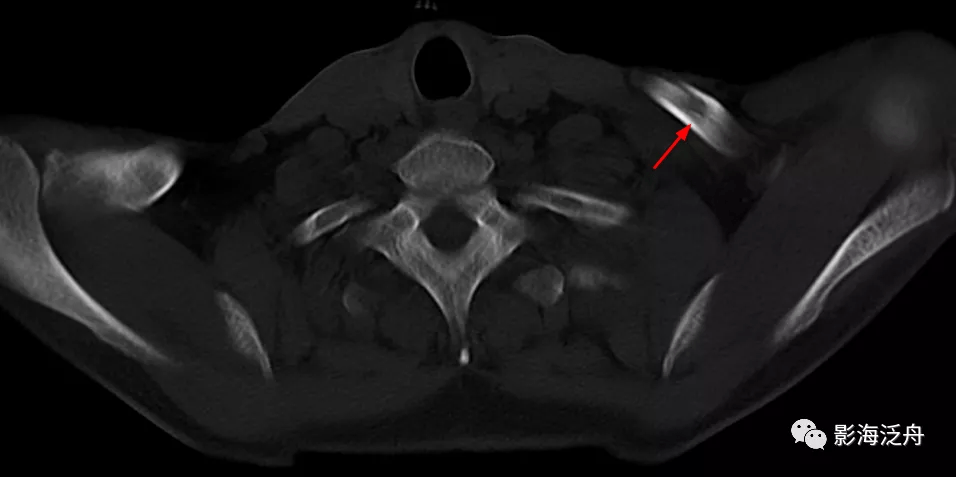

病例三:男 , 68岁 , 外伤后1天 , 左侧胸痛不适前来就诊 。

该患者扫描不规范 , 最上方层面仅包括了锁骨的一部分 , 但正是这仅有的两个层面显示左侧锁骨骨皮质不连续(红箭) , 由于该患者的图像是厚层为5mm , 所以骨折线显示的不是特别清晰 , 再加上该患者其余胸廓及胸椎骨质结构均未见明显骨折征象 , 所以稍不注意就会漏诊 。 对于这种扫描不规范的图像 , 如果不能重新检查 , 那就一定要非常细地去观察 。 很多纠纷就来自此类病例 。